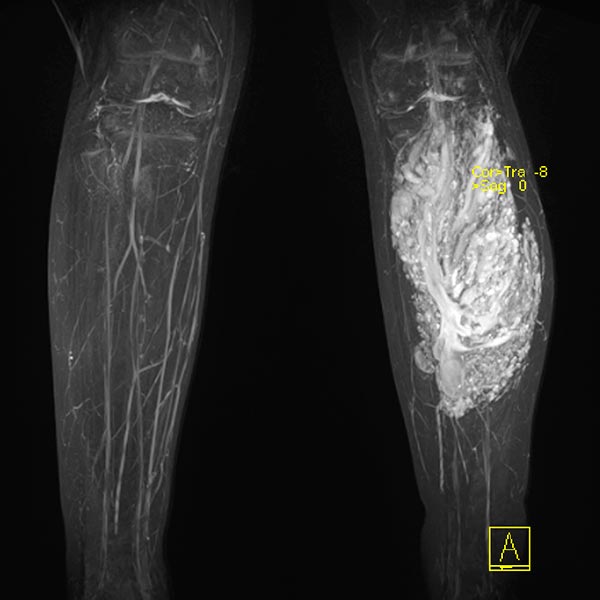

Coronal T1-weighted non-enhanced MRI shows an intramuscular, vascular lesion (isointense to the muscle) with marked interstitial hyperintense adipose tissue. This fatty tissue is more pronounced than would be usual in a normal venous malformation.

Contrast-enhanced MR angiography (MIP) shows complete enhancement of the venous malformation component in the left calf with contrast pooling.